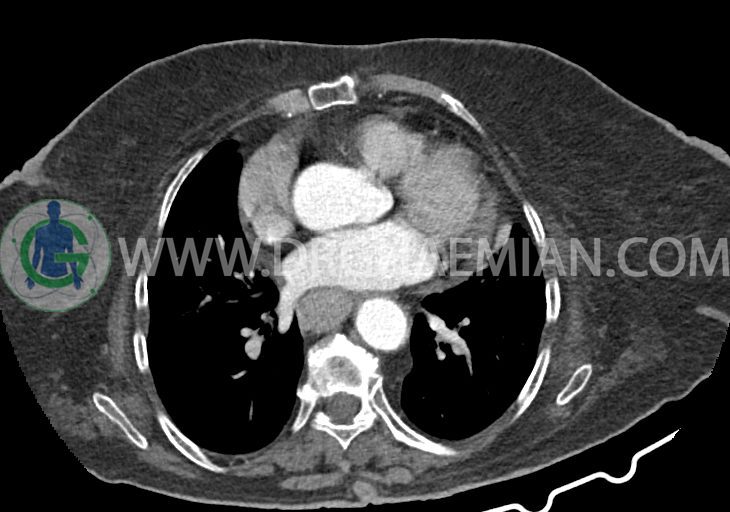

در سی تی اسکن اسپیرال ریه و مدیاستن – شکم و لگن با و بدون کنتراست خوراکی و وریدی (مولتی دیدکتور 16 با مقاطع ظریف و بازسازی های ساژیتال و کرونال):

–کاردیومگالی همراه با pericardial effusion خفیف

–یک ندول به ابعاد 19x18mm با حدود اسپیلوکه در سگمان لترال RML و دو ندول کوچکتر در مجاورت فوقانی آن به اقطار 6mm و 5mm ( مطرح کننده کارسینوم برونکوژنیک یا متاستاز )

–لنف نودهای non significant مدیاستینال با حداکثر SAD=6mm در فضای پره کارینا

–آئورت صعودی دیلاته به قطر 38mm